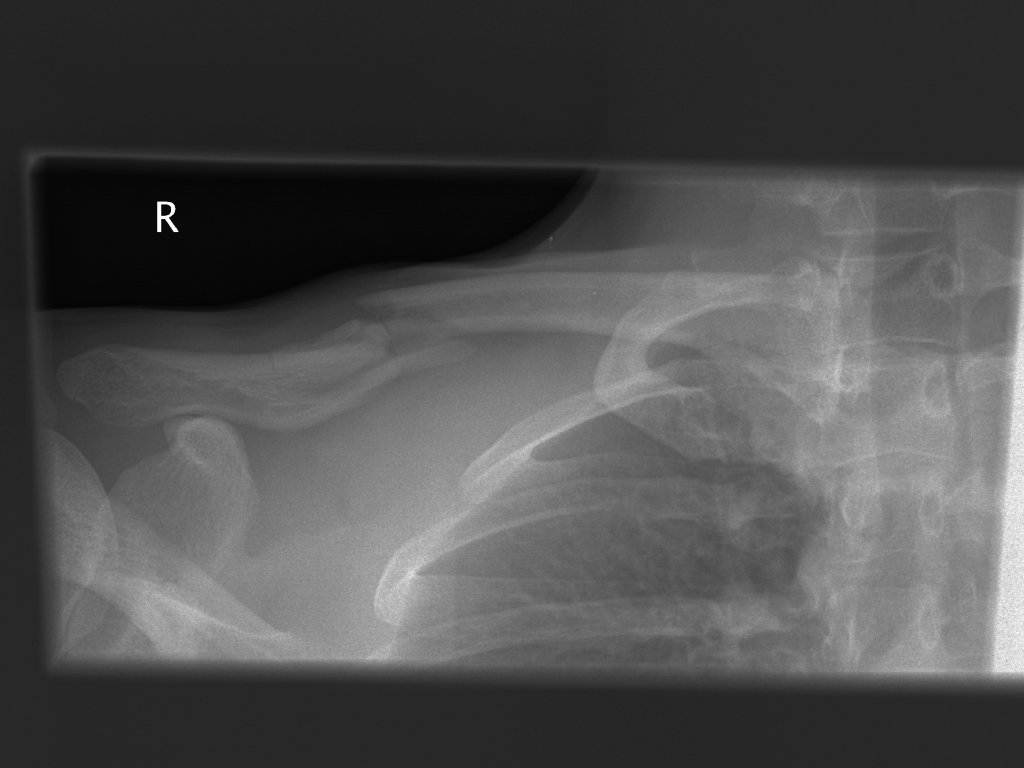

Clavicula-Fraktur (23./25. Juli/2. August 2007)

Image00002.web.jpg